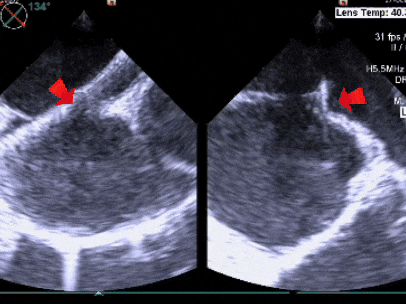

经食道超声所见:房间隔总长度约41mm。房间隔中部局部呈瘤样向右房膨出范围约11×19mm,房间隔中部回声中断约11×9mm,缺损上缘距房顶约17mm,缺损下缘距二尖瓣约10mm,缺损后下缘距下腔静脉约21mm,缺损后上缘距上腔静脉约13mm,短轴切面前残端0mm,后残端24mm。

超声提示:房间隔缺损(II孔型),房间隔膨胀瘤形成。

测量膨出瘤基底宽19.61mm,深7.00mm

房间隔总长44.22mm,缺损大小14.80mm

超声可见房间隔连续中断,彩色多普勒可见过隔血流